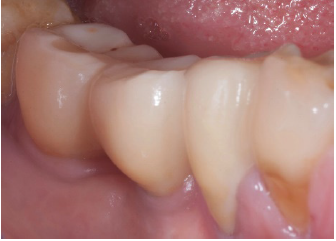

flap (Figure 10). In the next two pictures (Figure 11&12) we can

see the final restoration, a screwed in monolithic zirconia two unit

bridge, that fits well the previously edentulous ridge and offers a

very natural and bio-mimetic emergence profile. At last (Figure

Figure 11:Final restoration in place.

Figure 12:proper emergence profile.

Ridge defects have always been a challenge for the clinician and many surgical options and bio-materials have been advocvated for its treatment. In recent years the cortical lamina technique has surfaced as one of the techniques that reliably works in the solution of such problem. The case presented in this article had at baseline an horizontal ridge defect that would have not suggested the use of dental implants. Following ridge augmentation with a Xenograft covered with the cortical lamina it was possible to insert standard diameter implants and later to restore them. An important point is that even after four years of occlusal loading the regenerated bone does not show any kind of remodeling and/or resorbtion, thus confirming the efficacy of this treatment modality for horizontal ridge defects.